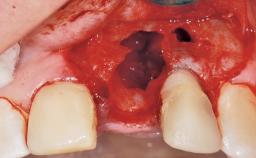

A 30-year-old female patient had lost tooth 21 and was referred to our clinic for consultation and treatment. Due to advanced apical infection, tooth 21 had been extracted two months earlier at another clinic and an acrylic-resin tooth had been bonded to the adjacent teeth. The patient desired implant treatment to avoid any damage to the adjacent natural teeth. While the patient had no history of any systemic disorder, she was a heavy smoker and exhibited medium to advanced periodontitis in the entire jaw. After the initial treatment to achieve a pocket probing depth of less than 4 mm and no bleeding on probing, a decrease in the height of the papillae mesial and distal to the extraction site and overall gingival recession were observed.

Soft Tissue Anatomy Intact Defective

Bone Volume Horizontally and vertically sufficient Horizontally deficient Deficient vertically or deficient vertically AND horizontally

Bone Volume Deficient horizontally, requiring prior grafting

Soft Tissue Grafting Simultaneous